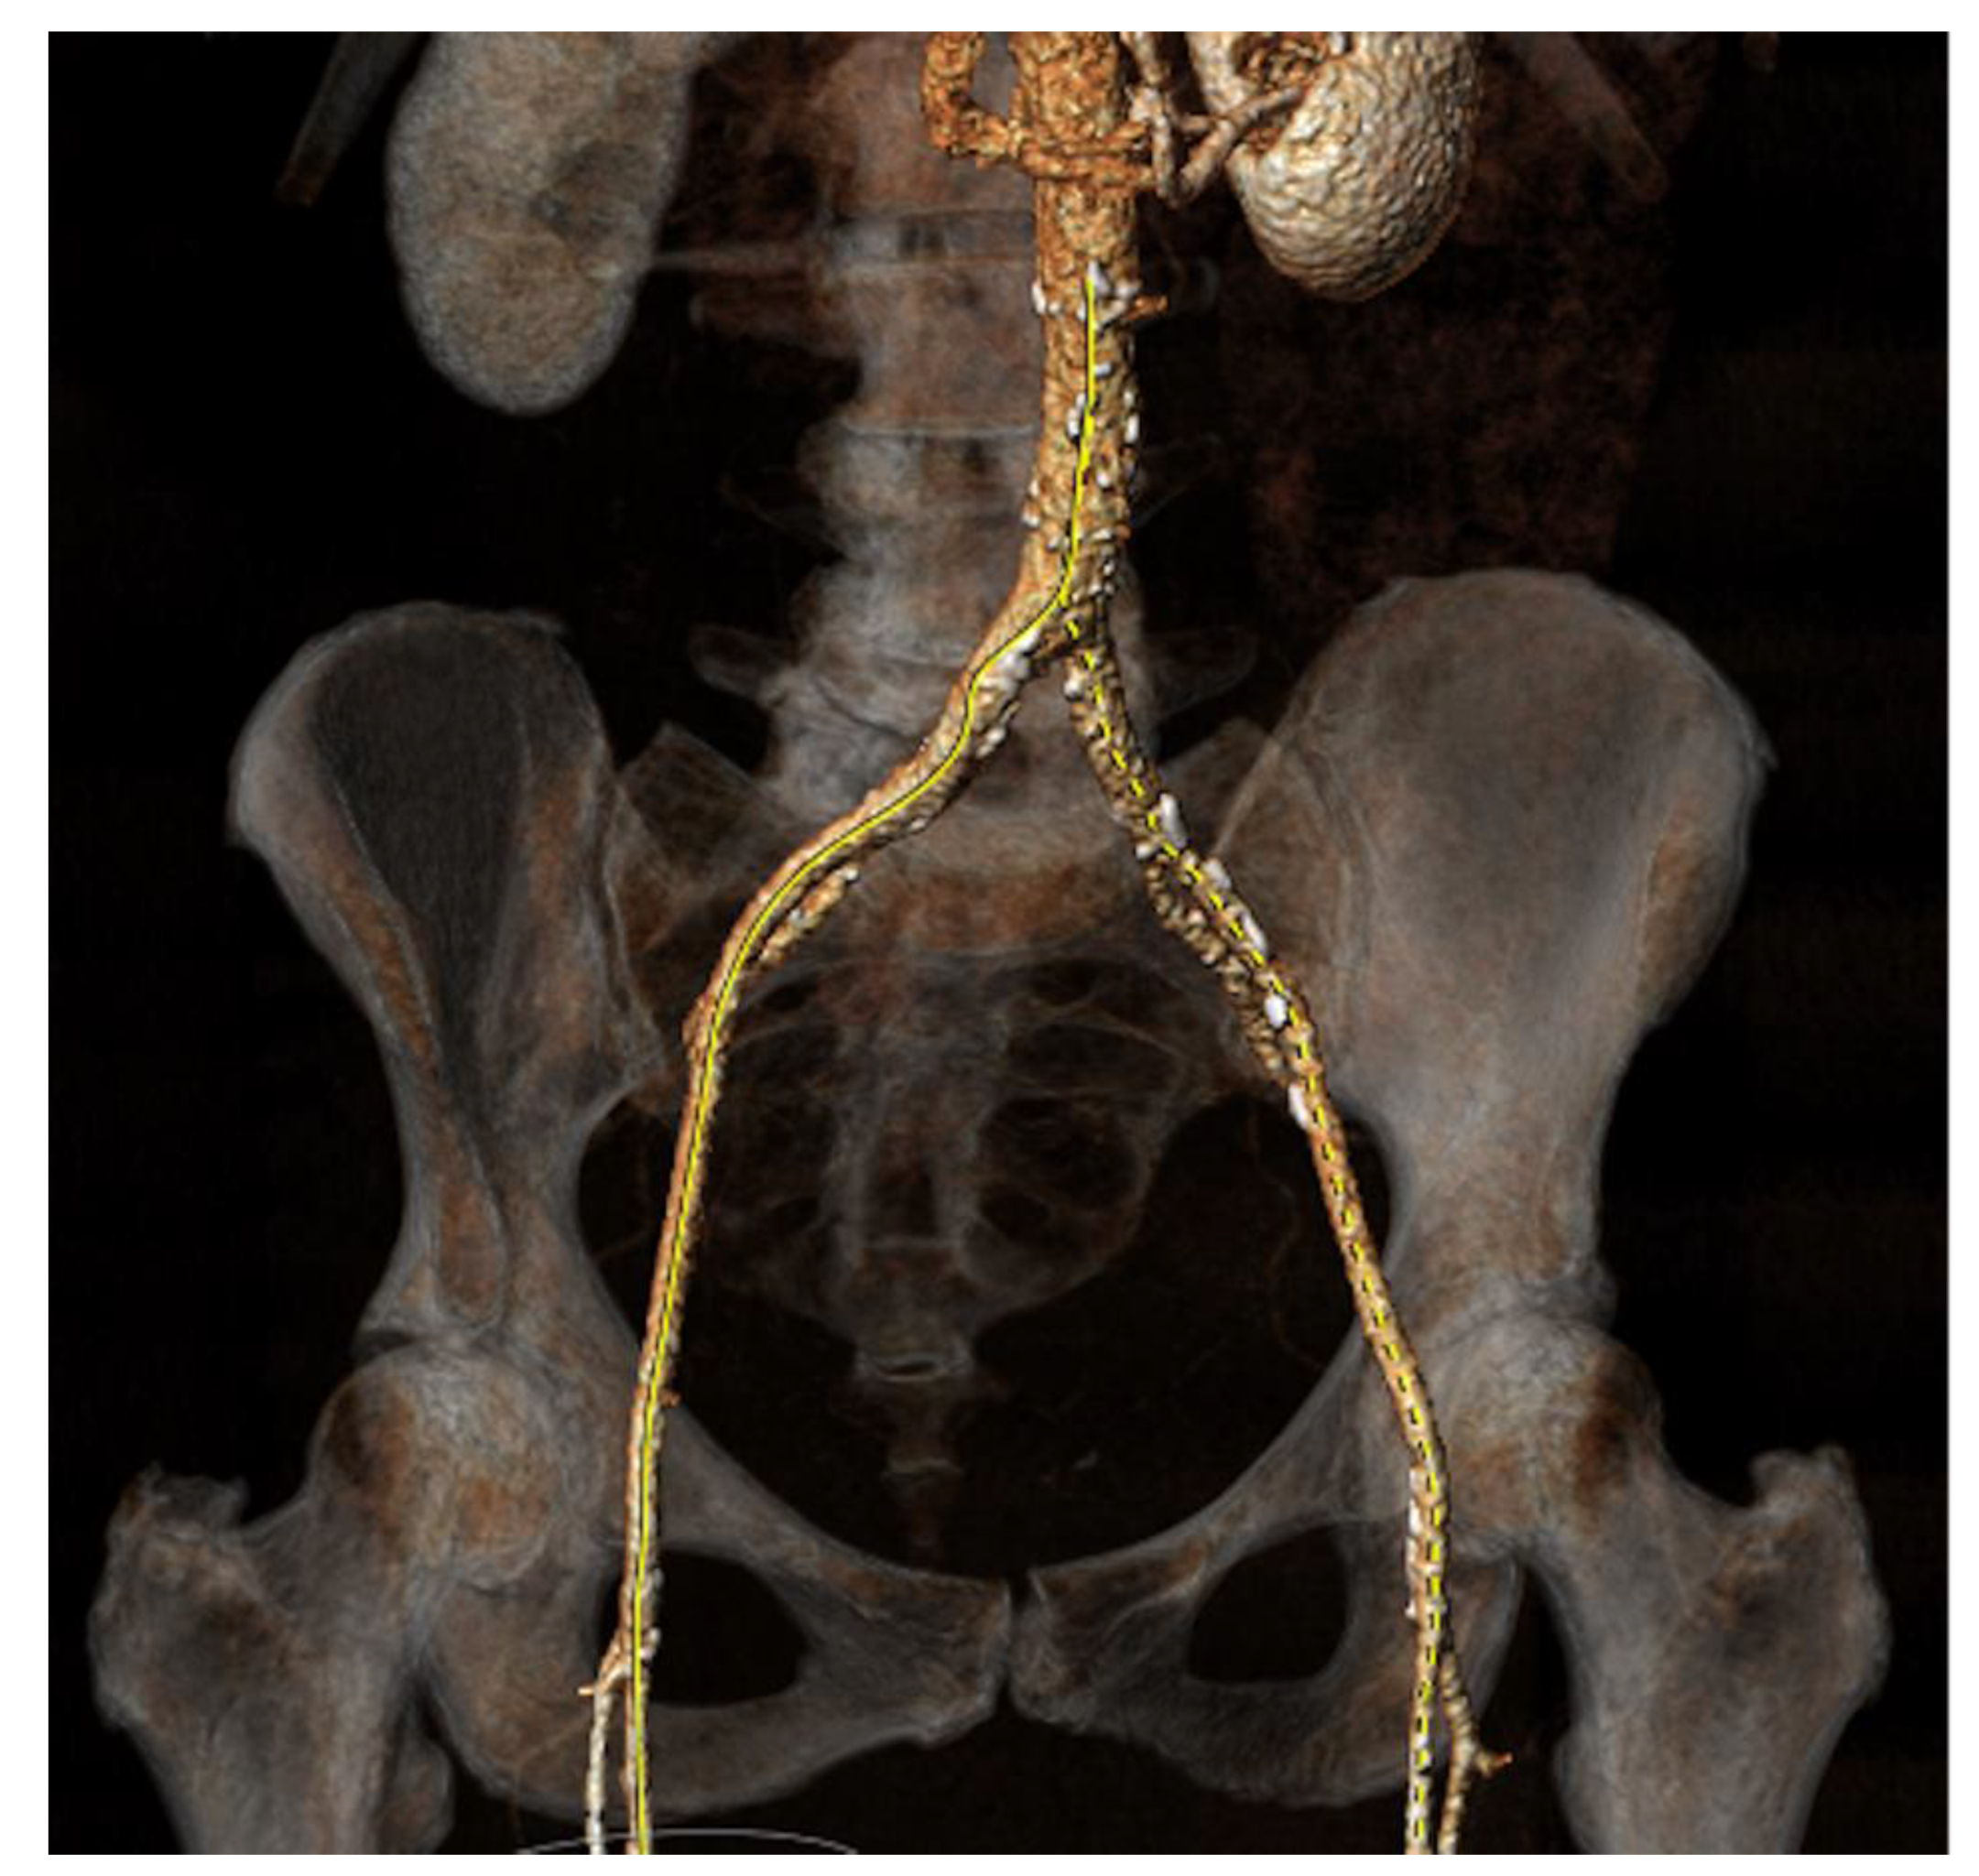

Aortic stenosis is the most common valvular heart condition in the UK, with a prevalence of almost 1.5% of the population aged >55 years-old suffering from severe disease [91]. Historically, the only definitive intervention was surgical valve replacement however development of the transcatheter approach has progressed to the degree that in 2024 it was shown to be non-inferior to surgical valve replacement even for low-risk surgical candidates [92]. The key variables to assess during TAVI planning include access anatomy (classically with a femoral approach), size of aortic root, prediction of optimal fluoroscopic angles for valve deployment, and assessing risk of coronary artery occlusion, and cardiac CT is able to provide all of these as depicted in figures 4a – 4d below [93].

Figure 4. a: CT Angiography for TAVI planning, showing a good transfemoral approach for a trans-catheter valve.

The Society of Cardiovascular Computed Tomography released a consensus document in 2019 advocating the optimal protocol and how all relevant information can be gathered with one administration of contrast [94]. The thoracic element of the scan requires ECG-gating to reduce motion artefact and allow precise measurements. Annular measurements are taken (maximum, minimum, and perimeter) to allow for prosthesis-sizing and reduce the chance of mismatch and its related complications [90]. The coronary ostium height is another vital parameter as low origin of the coronary arteries above the aortic valve leads to a greater risk of ostial occlusion, for which mortality is high [95]. Additional information is given regarding valve morphology and calcifications. TAVI is occasionally used in bicuspid aortic valves, with similar outcomes at 1 year [96] however aspects such as raphe with calcification extending into the left ventricular outflow tract are also important to note due to their association with paravalvular leak [97]. Finally for TAVI, vascular access is evaluated. The transfemoral approach is most common, however if this is not feasible due to tortuosity, caliber, or calcification of iliofemoral vessels, CT can instead assess subclavian or carotid measurements [90]. In summary, CT provides an enormous amount of information for planning all aspects of TAVI.